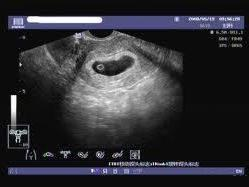

摘要:空孕囊的十個(gè)征兆包括停經(jīng)、早孕反應(yīng)減弱或消失、子宮大小不符合實(shí)際孕周、無(wú)胚芽及胎心搏動(dòng)、孕酮和HCG值偏低等。早期識(shí)別與應(yīng)對(duì)空孕囊至關(guān)重要,建議孕婦及時(shí)就診,通過(guò)B超和血液檢查確診。一旦確診為空孕囊,需采取相應(yīng)措施,如終止妊娠或?qū)で筢t(yī)生的專業(yè)建議。注意保持良好的心態(tài),遵循醫(yī)生的建議,以確保母嬰健康。

空孕囊是指孕婦在妊娠早期,胚胎發(fā)育異?;蛲V拱l(fā)育,導(dǎo)致孕囊內(nèi)沒(méi)有胚芽或胎心的情況,對(duì)于期待寶寶的家庭來(lái)說(shuō),空孕囊的出現(xiàn)無(wú)疑是一種打擊,了解空孕囊的征兆,早期識(shí)別并采取措施,對(duì)保障母嬰健康具有重要意義,本文將為您詳細(xì)解析空孕囊的十個(gè)征兆,以便您及時(shí)察覺(jué)并處理。

通過(guò)B超檢查發(fā)現(xiàn)胚胎未按照正常時(shí)間發(fā)育,如未按時(shí)出現(xiàn)胚芽、胎心等,可能是空孕囊的表現(xiàn)。